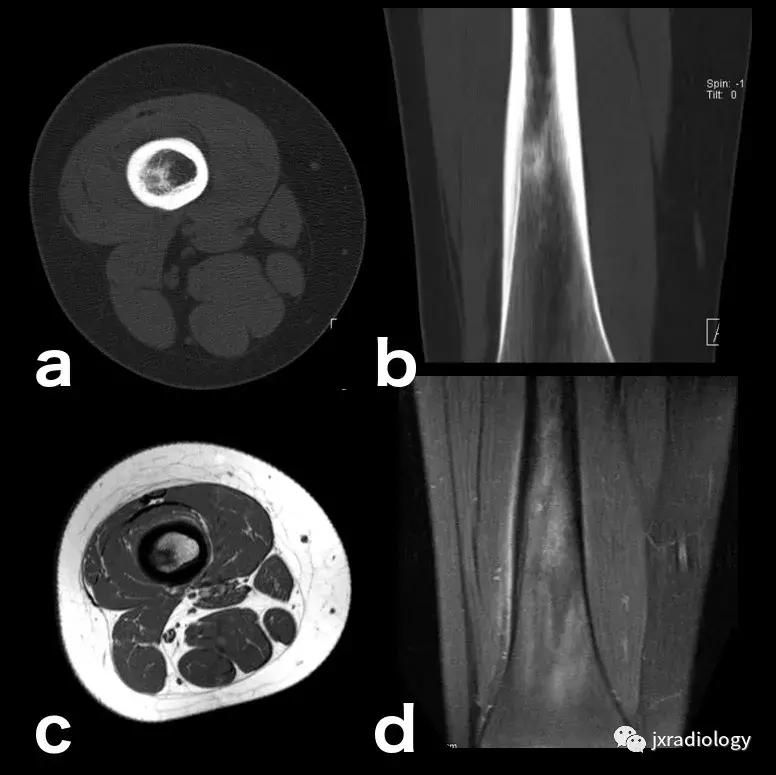

图24:骨样骨瘤:在这些良性肿瘤中,水肿可以继发于前列腺素E2引起的炎症反应(a,b:横断位和冠状CT扫描; c,d:横断位T1-WI和冠状位PD-FS-WI)。